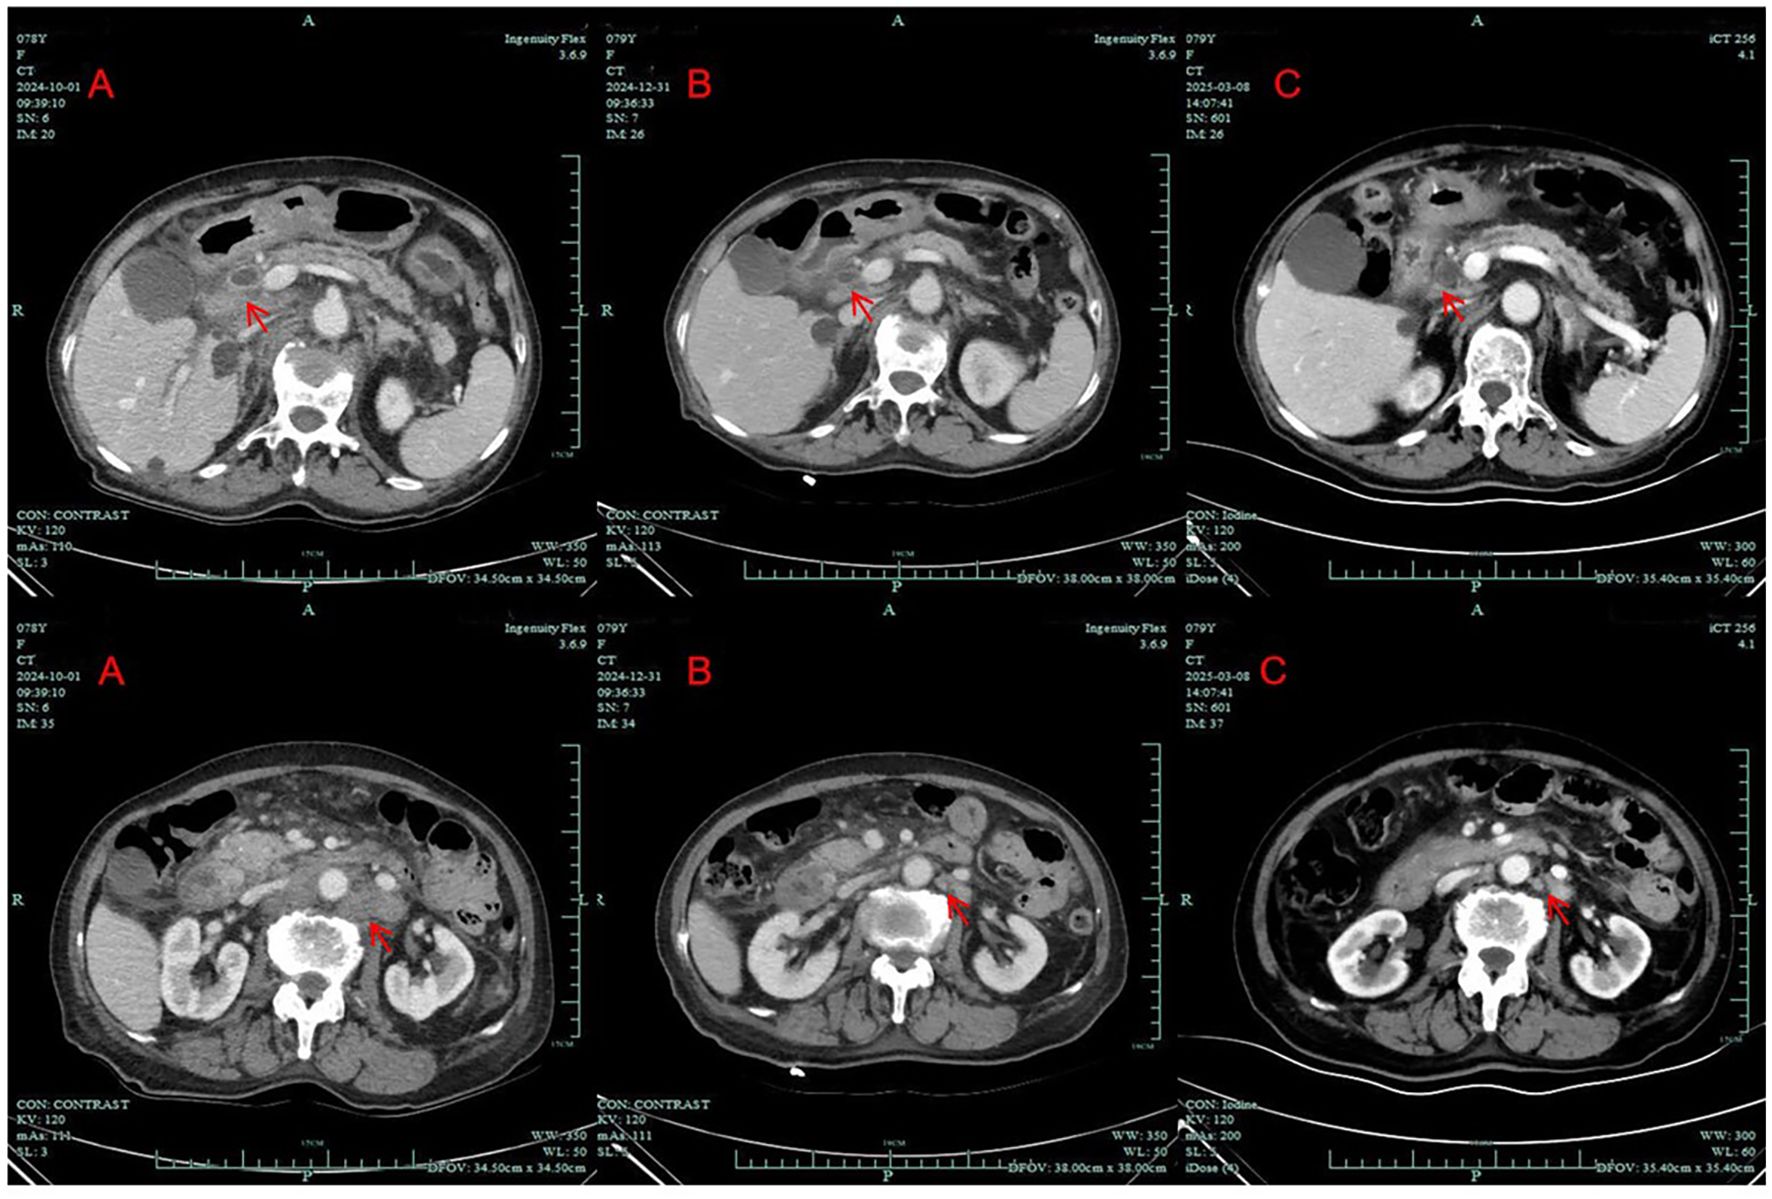

Despite the success of anti‑BRAF therapy in melanoma, data from randomized clinical trials are lacking for targeted therapy against BRAF mutations-typically the V600E variant-in pancreatic adenocarcinoma, which is associated with a poor prognosis under traditional cytotoxic chemotherapy. Here, we report a case of an elderly patient with advanced pancreatic adenocarcinoma harboring BRAF V600E mutation who received low-dose dabrafenib and trametinib achieved satisfactory clinical outcomes. We report a 78-year-old female with BRAF V600E-mutant pancreatic adenocarcinoma. The patient was diagnosed with AJCC clinical stage Ⅳ(cT3N2M1) pancreatic adenocarcinoma and she declined chemotherapy, considering her advanced age. Due to the BRAF V600E mutation, the patient was started on BRAF-and MEK-inhibitors (dabrafenib/trametinib). CT scans showed PR on December 31, 2024 and repeated CT scans showed SD on May 26, 2025. Until the writing of the case draft, the patient had achieved 8 months of PFS. The present case suggests that dose-adjusted dabrafenib combined with trametinib might be a potentially effective treatment strategy for elderly patients with advanced pancreatic adenocarcinoma harboring BRAF V600E mutations.